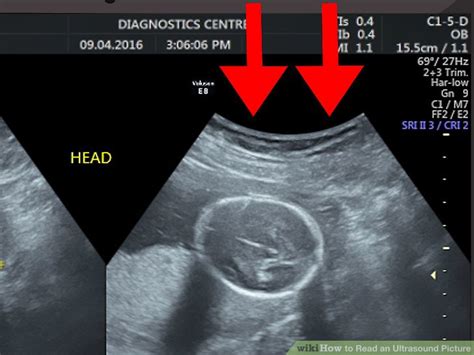

How To Read Sonogram Picture. Web learn how to interpret and read ultrasound images, including understanding the different types of scans and identifying key features on the images. Next to it is the date and time the ultrasound was taken, also found below the name of the diagnostics clinic.

This understanding will make it easier for you to see other details in an ultrasound image. You need to understand that white is solid and black is liquid. Meanwhile, the number found under the name in a pregnancy ultrasound is gestation age. In an ultrasound of a uterus, what you see at the top is the outline of tissues above the uterus. Web to start, you should know that the topmost part of a sonogram picture contains information about a patient. A computer translates the ultrasound waves into an image. A healthcare provider then reads the images to help diagnose the issue or problem at hand. Web the top of an ultrasound image depends on where the ultrasound probe is placed. The various shades of black, white and even gray can tell users the density of the tissue that the sound waves pass through. Web learn how to interpret and read ultrasound images, including understanding the different types of scans and identifying key features on the images.

A healthcare provider then reads the images to help diagnose the issue or problem at hand. The very top is where the probe rests, so the image shows what the organs and fetus look like from the side, not the top. Web sonography uses a device called a transducer on the surface of the skin to send ultrasound waves and listen for an echo. A healthcare provider then reads the images to help diagnose the issue or problem at hand. Color an ultrasound or sonogram picture is a black and white photograph, so they all look the same to someone who doesn't know much about how to read an ultrasound. Web start at the top of the image, and work down. Follow our expert tips for a better understanding of your ultrasound results. Web so the first step to help you read the ultrasound image is to be familiar with the anatomy that you are imaging. This understanding will make it easier for you to see other details in an ultrasound image. The denser the tissue, the brighter it will appear on an ultrasound. Further down the image, you can see deeper into the uterus and the lining.